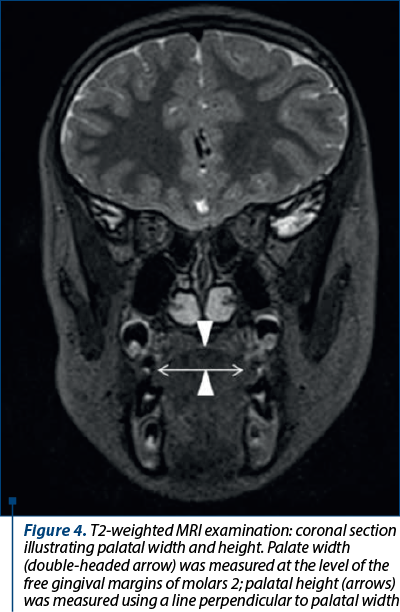

Various measurements of velopharyngeal structures (including hard palate length, soft palate length, velopharyngeal depth, palatal width and height; Figure 4) can be made on MRI sections. According to Ruda et al.(16), the choice of treatment method for velopharyngeal insufficiency depends on numerous factors that can be evaluated by MRI; of these, of great importance are the symmetry and degree of separation between the veil and the pharynx, and the configuration of the velopharyngeal muscles.

A recent study by Ali et al.(17) demonstrated that resting velopharyngeal MRI measurements in cleft palate patients correlated with their speech performance; velar thickness had a moderate significant positive linear correlation with the degree of velar motion and global speech intelligibility(17).

Measurements provided by MRI images help surgeons choose the most appropriate approach to optimize velar coverage in separating the nasopharynx and oropharynx during phonation.